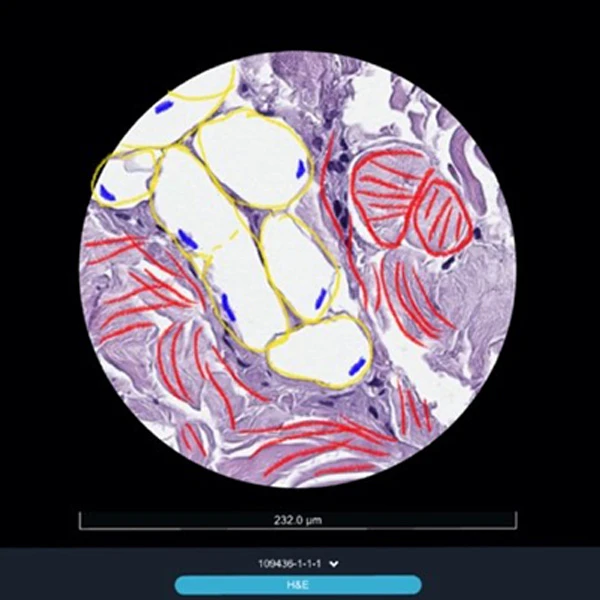

Рис. 1. Виды соединительной ткани в панч-биоптате после курса сеансов воздействия, окраска гематоксилин+эозин: жировые дольки (1) с адипоцитами (1А), строго ориентированные пучки волокон (2Б) в стромальных трабекулах (2). Голубыми стрелками указаны длины адипоцитов.

Прежде всего обращает на себя внимание реакция со стороны клеток жировой ткани: при практически неизменном количестве самих жировых клеток средний размер (объем) каждой жировой клетки существенно сократился почти вдвое.

Предположительно такой эффект достигается за счет активного высвобождения содержимого самих жировых клеток и транспортировкой его в кровеносное русло мелких сосудов соединительной ткани.

Косвенно это подтверждается второй группой зафиксированных изменений на фоне применения аппарата Beautylizer (RSL-скульптурирование*): увеличении просвета сосудов микроциркуляторного русла на единицу площади зоны, что свидетельствует об активации не только функциональной части микроциркуляторного русла, но и стимуляции работы как коллатерального кровообращения, так и основного. Активное кровоснабжение позволяет не только снизить задержку жидкости в тканях и формирование отеков, но и простимулировать активную работу клеток, продуцирующих полезные белковые компоненты соединительной ткани3.